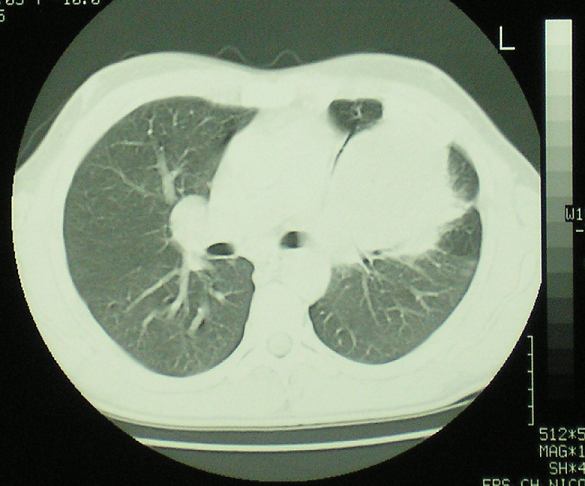

Des atteintes vasculaires graves notamment les anévrysmes des artères pulmonaires peuvent compliquer le syndrome de Behçet. Ces atteintes sont rarement révélatrices entrainant un retard diagnostique. Patient âgé de 32 ans, hospitalisé pour des épisodes récidivants d'hémoptysie de faible abondance. L'interrogatoire a trouvé la notion d'aphtose bipolaire récurrente évoluant depuis deux ans. L'examen physique a objectivé une apyrexie, un aphte buccal, une cicatrice d'aphte génital, des lésions de pseudofolliculite au niveau du dos et un test pathergique positif. L'examen ophtalmologique, neurologique et abdominal était sans anomalies. Sur le plan biologique, il n'avait pas de syndrome inflammatoire. Il avait une anémie normochrome normocytaire avec une hémoglobine à 10,5 g/dl. La radiographie de thorax a révélé une opacité homogène de contours réguliers para-hilaire gauche. L'angio-scanner thoracique a éliminé une origine parenchymateuse qui peut être en rapport avec une néoplasie, une vascularite ou une infection pulmonaire. Il avait plutôt un anévrysme géant au niveau de l'artère pulmonaire gauche de 10 cm de grand axe. Le diagnostic de syndrome de Behçet a été retenu devant l'association d'une aphtose bipolaire récurrente, de pseudofolliculites et un test pathergique positif. L'anévrysme de l'artère pulmonaire rentre dans le cadre d'un angio-Behçet. Il a reçu un traitement médical qui s'est basé une corticothérapie à forte dose avec diminution progressive des doses, des boli mensuels de cyclophosphamide et colchicine. Il n'a pas présenté de récidive des hémoptysies. L'anévrysme a discrètement diminué de taille. Un traitement chirurgical lui a été prévu.